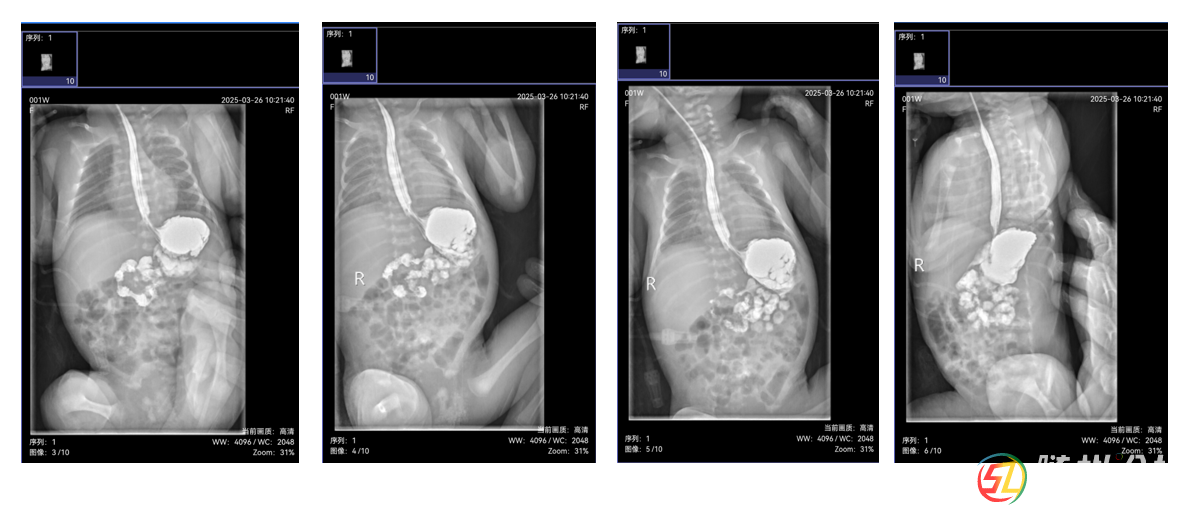

由于新生兒消化道畸形診斷技術(shù)要求高,隨州市中心醫(yī)院新生兒科副主任涂小瓊迅速啟動(dòng)多學(xué)科協(xié)作機(jī)制,聯(lián)合本院超聲影像科副主任醫(yī)師涂朝霞行幽門(mén)管超聲檢查、醫(yī)學(xué)影像科副主任楊永剛行上消化道造影檢查,并積極聯(lián)系武漢兒童醫(yī)院新生兒內(nèi)科主任曾凌空教授、放射影像科主任彭雪華教授開(kāi)展遠(yuǎn)程會(huì)診。

會(huì)診中,彭雪華教授詳細(xì)解讀影像資料,明確診斷為“可復(fù)性胃翻轉(zhuǎn)”,排除了幽門(mén)肥厚;曾凌空教授結(jié)合患兒情況,制定了科學(xué)的喂養(yǎng)方案和后續(xù)治療計(jì)劃。此次會(huì)診不僅為朵朵的康復(fù)指明了方向,也為隨州市中心醫(yī)院積累了新生兒消化道畸形診斷的寶貴經(jīng)驗(yàn)。